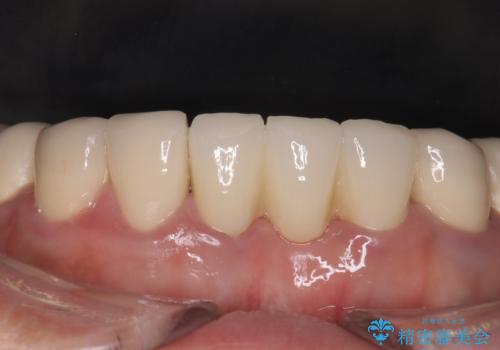

抜歯をしているため、その部位の治癒を待ってからブリッジを装着するので、2-3か月ほど治療期間を必要としました。